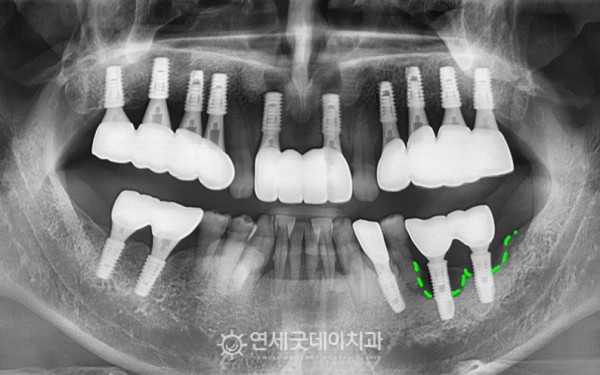

치근단염이 관찰되었던 #35 부위 발치와

타원 임플란트를 안정적으로 제거하였으며

제거한 픽스쳐 표면으로

세균이 가득하게 자리 잡은 모습입니다.

제거 후에는 추후 새로운 임플란트를 안전하게 심고

두툼한 잇몸뼈 기반을 만들어주기 위해

뼈이식을 진행했습니다

환자분은 흡연 조절이 어려우셔서

치료 과정이 쉽진 않았지만

그럼에도 잇몸뼈가 다시 자리잡고,

임플란트가 안정적으로 식립된 모습입니다.

치료전과 후를 보시면 완전히 내려 앉았던 잇몸뼈가

최대한 두툼하게 재생되며 잘 회복된 모습입니다.